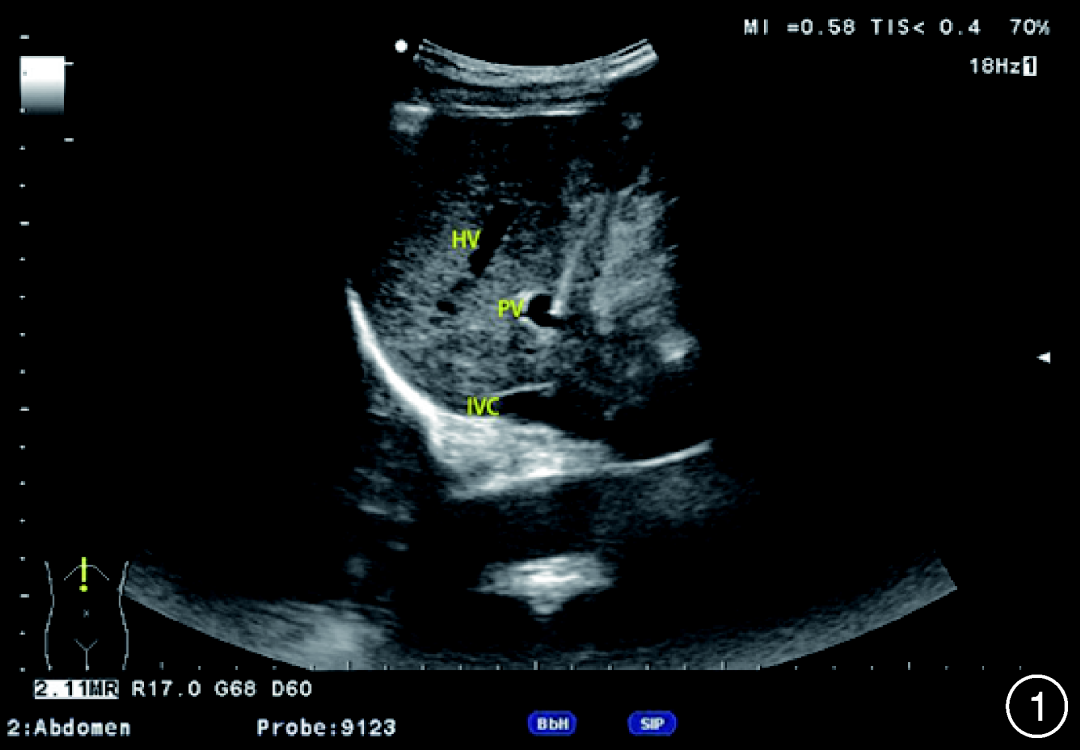

单纯的门静脉压力测定易受腹腔内压力、压力调零水平点的影响,故笔者所在的中心提出了“超声引导门静脉压力梯度(UPPG)”测定的方式,经皮经肝分别穿刺门静脉(图1)、肝静脉或下腔静脉肝段,测定门静脉自由压、肝静脉游离压或下腔静脉游离压,获得门静脉压力差,消除腹腔压力、水平调定点、人为操作等对门静脉压力的影响。自2020年10月正式开展工作以来,获得患者知情同意并纳入肝硬化失代偿期伴食管胃底静脉曲张或破裂出血患者共56例,完成门静脉压力测定56例,操作成功率100%,纳入的56例患者中,男43例、女13例,年龄(54.9±10.0)岁(29~76岁),其中乙型肝炎肝硬化35例、酒精性肝硬化13例、丙型肝炎肝硬化1例、自身免疫性肝炎肝硬化1例、药物性肝硬化1例、不明原因肝硬化5例,血小板计数(72±20.5)×109/L,凝血酶原时间(18.3±5.2)s,所有患者采用局部浸润麻醉,术中监测心率、血压、呼吸变化,操作时间(25.3±10.5)min,获得的门静脉压力(29.8±7.7)mmHg,肝静脉压力(9.0±3.8)mmHg,门静脉压力梯度(20.9±6.3)mmHg,术中或术后疼痛8例(其中1例需止痛治疗),操作中低血压1例(补液后缓解),一过性胸闷不适10例,术后2个月复查超声提示肝动静脉瘘1例,无其他术中、术后并发症。此法操作风险低,成功率高,可重复性高,在临床操作中有巨大前景。

注:HV指肝静脉;PV指门静脉;IVC指下腔静脉

1 超声定位下穿刺针经皮经肝穿刺进入门静脉